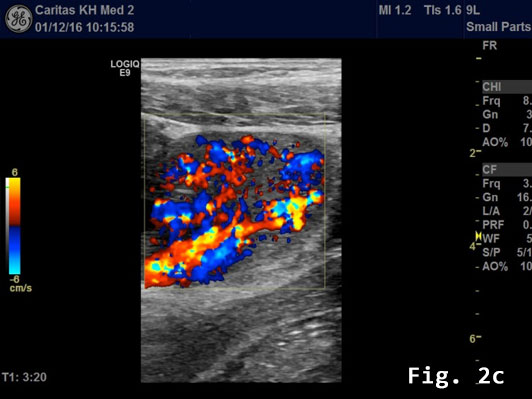

Transabdominal B-mode ultrasound (BMUS) confirmed a 40 mm sized heterogeneous hy-poechoic lesion infiltrating the sigmoid colon [Figure 2].

Endorectal endoscopic ultrasound of the sigmoid colon revealed transmural extension of the mass and confirmed the transcutaneous finding. The lesion was well vascularized [Figure 2].